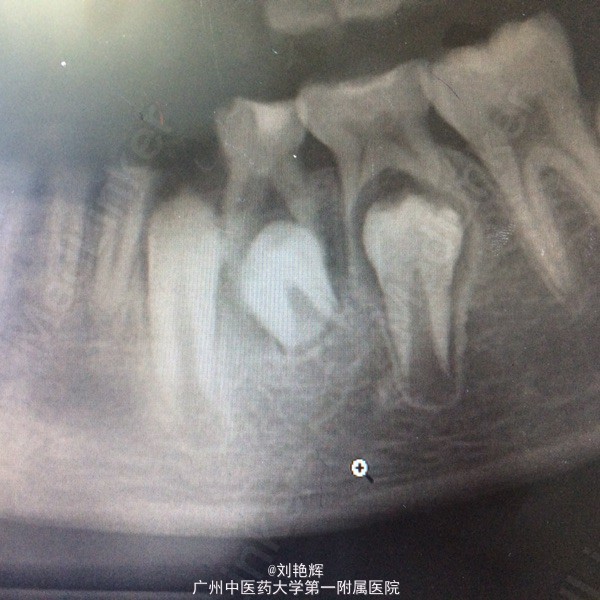

左下乳四合面充填物存,颊侧牙龈略肿胀,冷(-)扣(-) 辅助检查:全景片发现左下乳四根尖阴影,34发育异常

诊断:乳四慢性根尖炎 处理:拔除乳四

考虑要不要一起把已发育异常的34一并拔掉,以后35萌出后看情况正畸治疗,或者以后萌出后再拔,元芳,你怎么看?